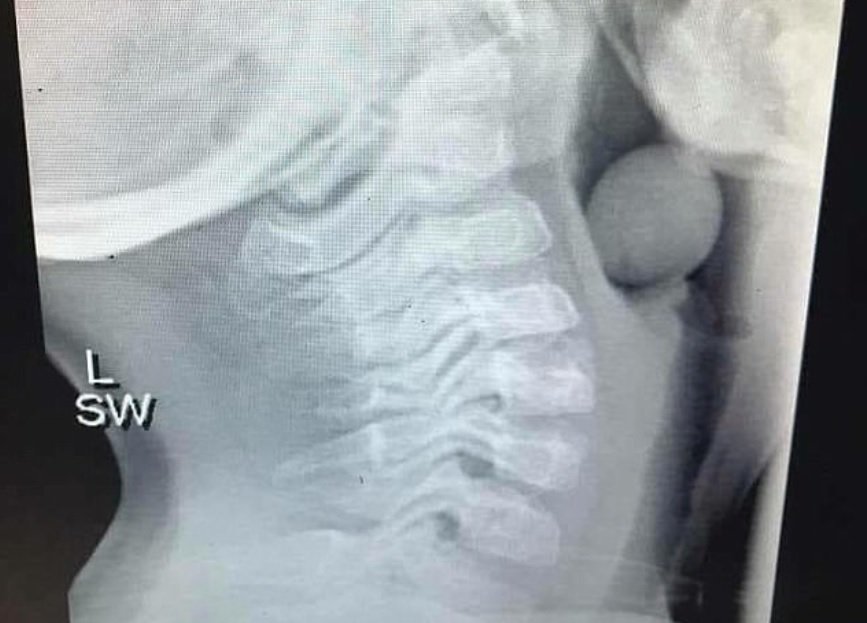

La revista médica BMJ publicaba un estudio titulado Archives of Disease in Childhood realizado por médicos de urgencias, donde se destacaba el peligro que puede suponer para niños menores de cinco años el comer uvas enteras. Los médicos británicos responsables de la publicación afirmaban que la mayoría de la población no es consciente de los riesgos de asfixia mortal en niños que implican algunos alimentos, incluyendo una fruta tan aparentemente inocente como la uva.

Los datos apuntaban que, efectivamente, las uvas son la tercera causa más frecuente de accidentes por ahogamiento con alimentos, en edades tempranas, por detrás de los caramelos y los perritos calientes. Y todo esto dentro de un contexto normal y cotidiano, alejado de la ingesta atropellada que se suele hacer en Nochevieja para conseguir engullir una uva con cada campanada.